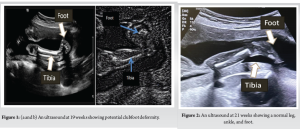

Out of the 2000 pregnancies, there were 1970 live births, with an overall incidence of CTEV at 0.355/100 live births. The median gestational age at the time of US was 19.64 weeks. Fetal anomaly scanning identified CTEV in 12 fetuses pre-natally. (Figure 1 & 2) Upon a review scan after 6 weeks, 2 patients were informed that the initial diagnosis was a misinterpretation, and the fetuses were normal. At birth, 7 cases were confirmed to have structural (bilateral) CTEV, while 3 cases were found to be positional deformities. (Table 1) During the study period, 10 feet were affected by clubfoot, with 3 cases being bilateral (6 feet) (Figure 3) and 4 cases being unilateral (4 feet). Among the neonates, 1039 (52.74%) were male and 931 (47.26%) were female. Post-delivery, all affected feet (10 out of 10) were treated using the Ponseti technique (Figure 4), and no additional open surgeries (posterior or posteromedial release) were performed on any of the patients. With a prevalence of 0.355, out of every 100 live-born infants, approximately 0.355 infants are born with CTEV. This means that in a population of 1,000 live births, approximately 3.55 infants would be expected to have CTEV. The PPV of the screening is 58.33%, meaning that when the test indicates a fetus has CTEV, there is a 58.33% chance that the fetus actually has a structural deformity that will require treatment using the Ponseti method. This indicates that about half of the positive diagnoses made by the US are confirmed as true positives upon further examination. The NPV of the test is 100%, indicating that when the screening test shows no signs of CTEV, it is certain that the fetus does not have the deformity. This high NPV demonstrates the test’s reliability in ruling out CTEV, ensuring no cases are missed. The sensitivity of the test is 100%, which measures the test’s ability to correctly identify all fetuses with CTEV. A sensitivity of 100% means that the screening test detected every case of CTEV, with no false negatives. This ensures that all affected fetuses are identified early. The specificity of the test is 99.75%, which indicates the test’s effectiveness in correctly identifying fetuses without CTEV. A specificity of 99.75% means that the test correctly identified 99.75% of the fetuses that did not have the deformity, with very few false positives.